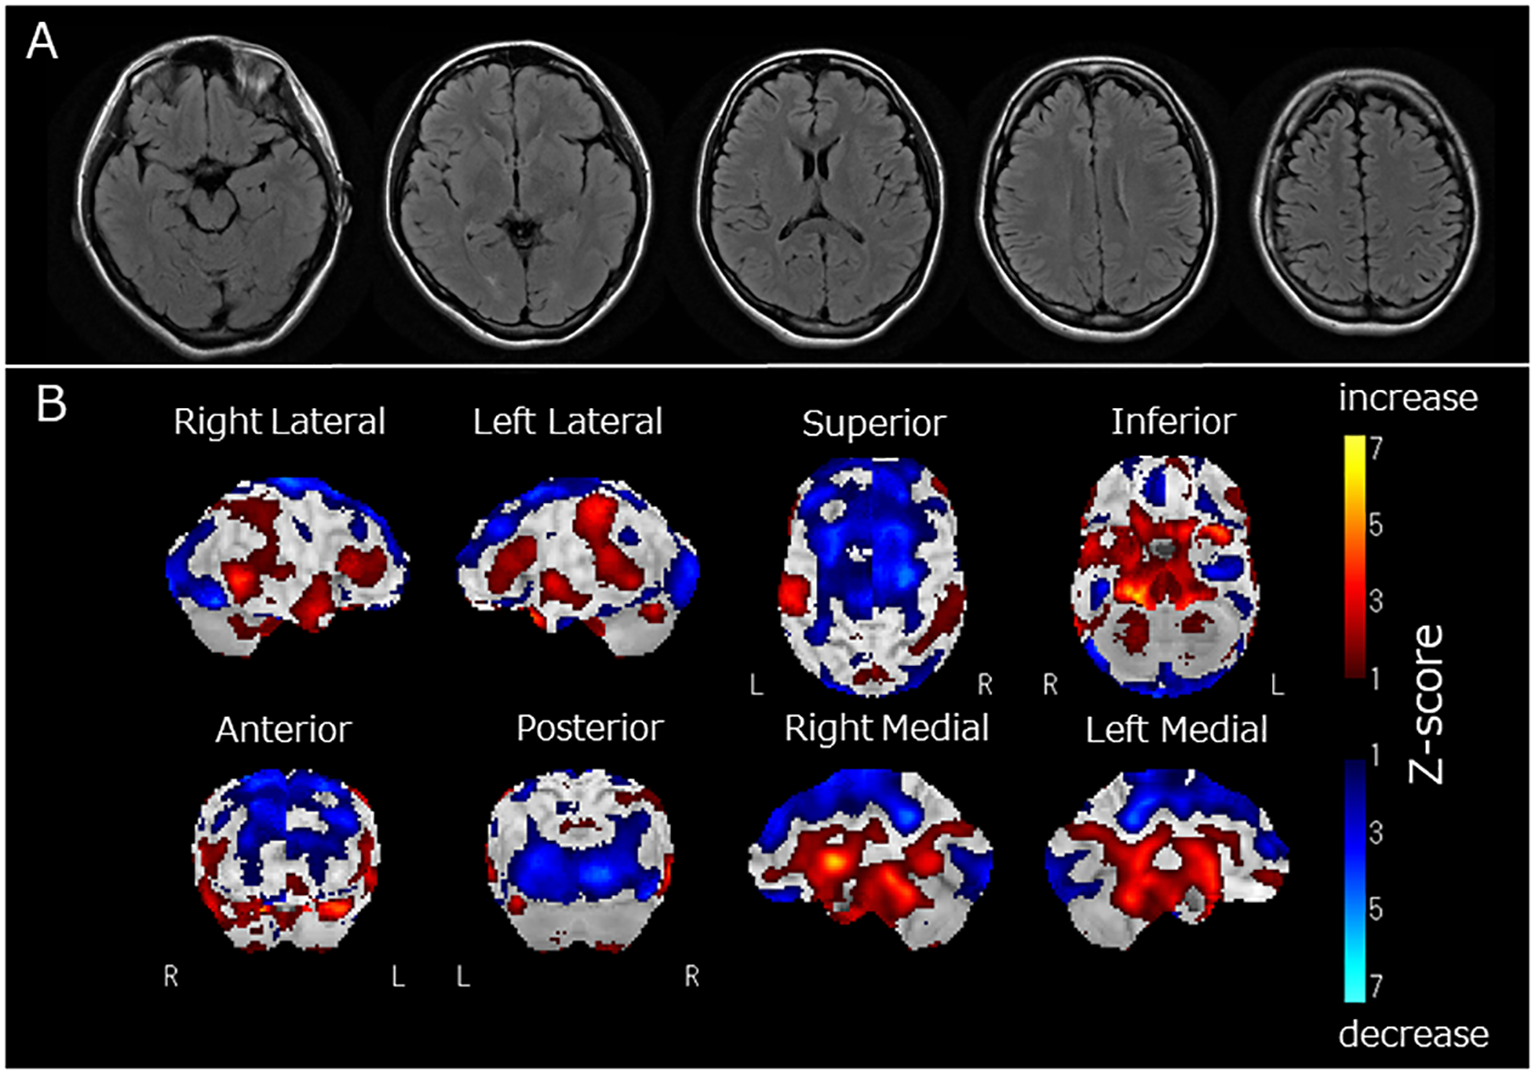

Figure 1

(A) Fluid Attenuated Inversion Recovery magnetic resonance imaging of the brain, (B) regional cerebral blood flow (rCBF) using single-photon emission computed tomography (SPECT) with 123I-iodoamphetamine. Fluid-attenuated inversion recovery magnetic resonance imaging revealed no apparent brain atrophy or high-intensity areas (A). SPECT using a 123I-iodoamphetamine was performed, and SPECT data were analyzed by 3D stereotactic surface projections (3D-SSP) included in “medi+FALCON version 1.4” (Nihon Medi-Physics Co. Ltd., Tokyo, Japan). Z-score maps of regional cerebral blood flow (rCBF) were created based using 3D-SSP. The SPECT images showed decreased rCBF in the occipital and frontal lobes (B). In contrast, rCBF increased in the basal ganglia and pons (B).

Two months after admission, she displayed pessimistic thoughts, suicidal ideation, Cotard delusions, and Capgras delusions such as “Other persons, who have the same facial features as my parents but who have been replaced, live in my home. My real parents are dead.” She attempted suicide by jumping or hanging because she believed that her entire family was dead and that there was no reason to live. Regional cerebral blood flow (rCBF) was evaluated using single-photon emission computed tomography (SPECT) with 123I-iodoamphetamine. rCBF was decreased in the bilateral frontal and occipital lobes and increased in the bilateral basal ganglia and pons (Figure 1B). Fourteen sessions of bilateral ECT were conducted. The decision to employ ECT was based on the urgent need to address frequent suicidal attempts. ECT has been recognized for its efficacy in preventing such attempts (13). Additionally, it has proven to be effective in treating autoimmune encephalitis (2). Two months and three months after admission, two serum examinations were conducted and both showed a strong positive result for anti-recoverin antibodies. After ECT, her psychiatric symptoms, including Cotard delusions, Capgras delusions, and suicidal thoughts, markedly improved. At 8 months, steroid therapy was discontinued, and the patient was discharged from the hospital after physical and verbal rehabilitation. One year after discharge, the patient remained in remission.

In this case, we observed Cotard and Capgras delusions. Cotard and Capgras delusions belong to delusional misidentification syndrome, caused by various organic brain diseases such as dementia, cerebrovascular disease, and encephalitis, as well as psychiatric disorders such as schizophrenia and depression (20, 21). These delusions are reportedly developed by two factors (20): abnormal perception leading to sensations of derealization or depersonalization, which is associated with dysfunction of the insular cortex, and abnormal rationalization towards external causes (Capgras delusion) and internal causes (Cotard delusion), which are related to dysfunction of the prefrontal cortex (3). The present case displayed decreased rCBF in the frontal and occipital lobes and increased rCBF in the basal ganglia and pons. Therefore, dysfunction in the prefrontal cortex, reflected as decreased rCBF, might be associated with the clinical features of Capgras and Cotard delusions observed in this case.